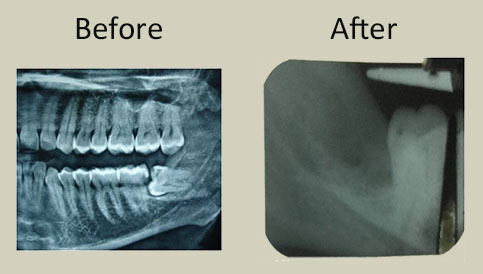

Images of cases done with prp

MOLAR IMPACTION